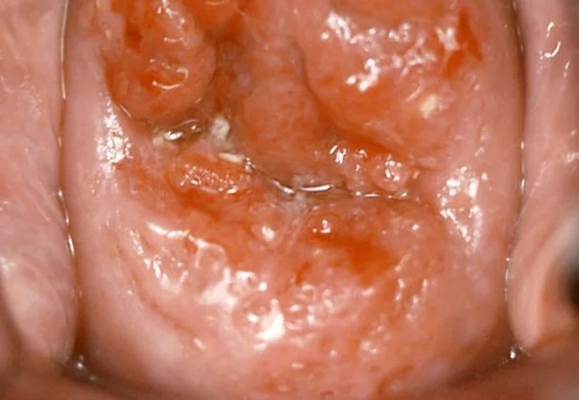

子宮頸糜爛圖片

宮頸糜爛 (9)